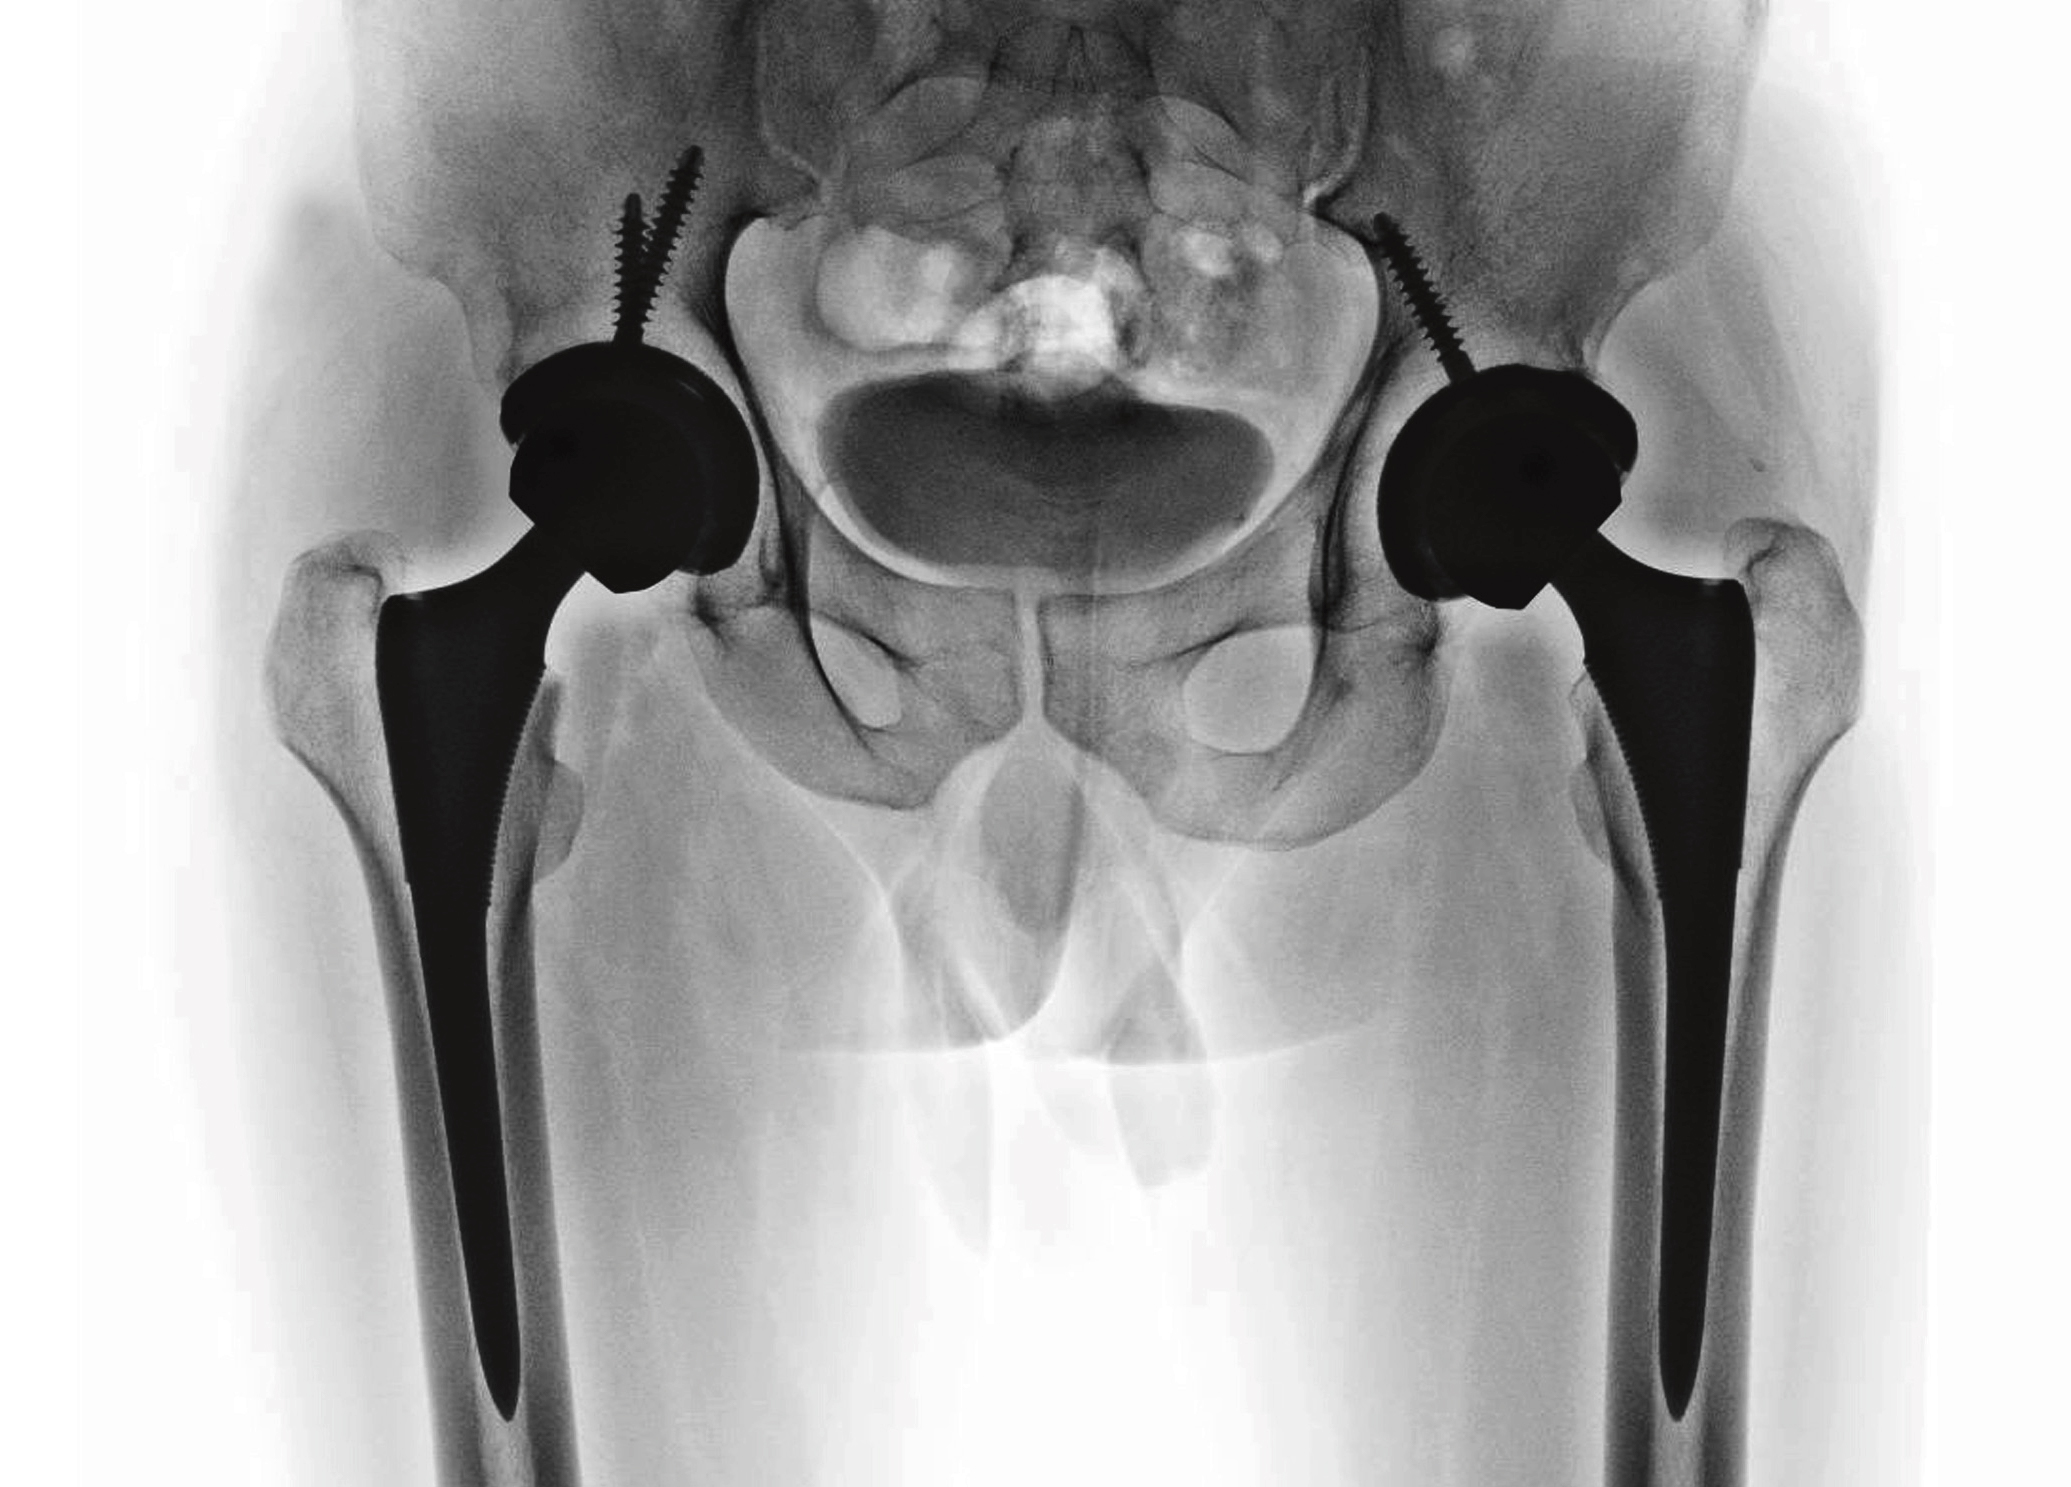

Delprotese er like bra som totalprotese ved lårhalsbrudd med feilstilling hos eldre. Dette viser en stor randomisert studie med et betydelig norsk bidrag.

Illustrasjon: Sittithat Tangwitthayaphum / iStock